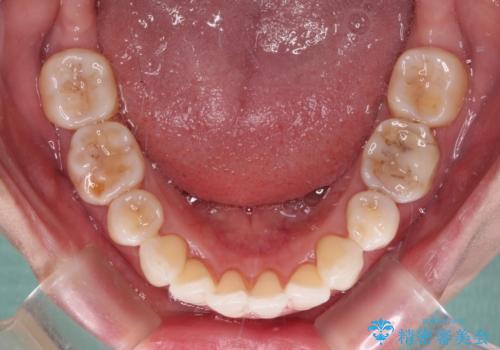

- 上の前歯の出っ歯を治したいとのことで来院された患者様です。

後戻りによる再矯正というもともあり、インビザラインを希望されていました。

上顎の歯は後方移動とIPR(歯と歯の間を削る)によって口元が引っ込むように、下顎は歯列全体の拡大とIPRによって上顎とバランスよく咬み合うように設計し、インビザラインにより治療を行うこととしました。

治療を開始して暫くして、勤務先から2年以上帰国することができず、それまでの移動がほとんど後戻りしてしまい、帰国後に再度後戻りをリカバリーするための治療を行うこととなりました。

5年以上の治療期間がかかりましたが、気になっている部分を改善することができました。